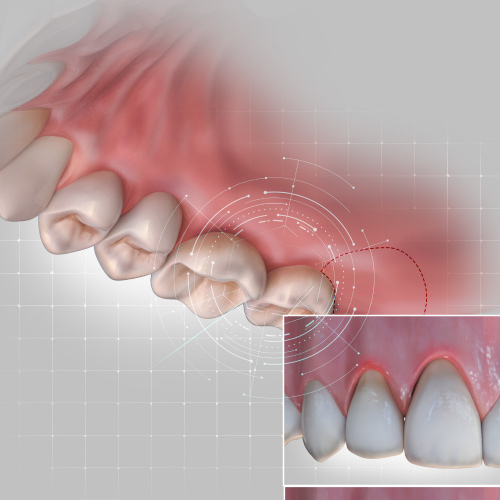

Implantology Pathways

Sunday, March 10, 2024

This Compendium eBook features features a continuing education (CE) article on the use of subcrestal implantoplasty for the treatment of peri-implantitis. This eBook also includes a case report article on a novel, minimally invasive technique to reconstruct class III sockets with simultaneo...